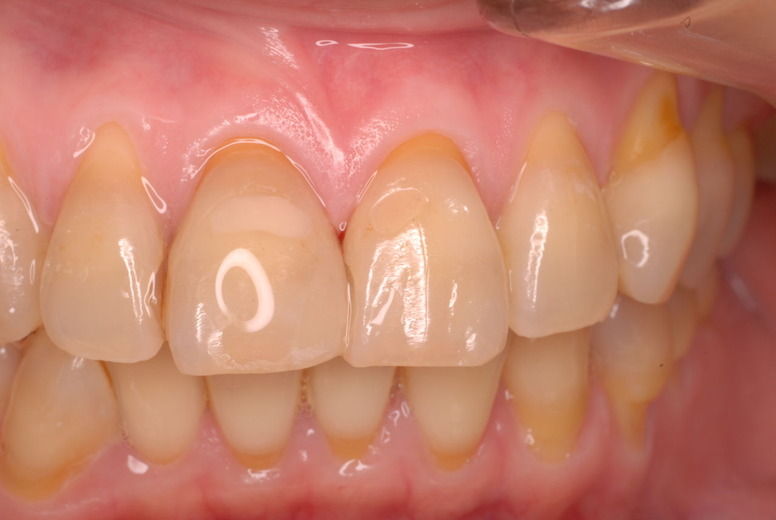

14年歯前、歯の神経が腐り、神経を除去したまま来なくなった現在大学生の女性

歯周病になっていましたが、少し色が黄色くなっているだけで比較的綺麗な歯の状態です。

平成9年来院神経を取り、同時に歯周病の話をしてそのまま来なくなっていたかたですが、たまたま一部欠けてきました。それで来院。